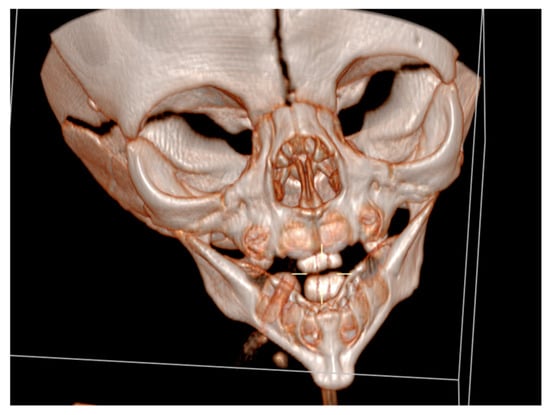

Cranial ultrasound showed no pathological findings, except for discretely hyperechoic periventricular white matter. A computed tomography of the facial region described the mandibula as hypoplastic and narrow (Figure 3).

Figure 3. A computed tomography of a narrow and hypoplastic mandibula.